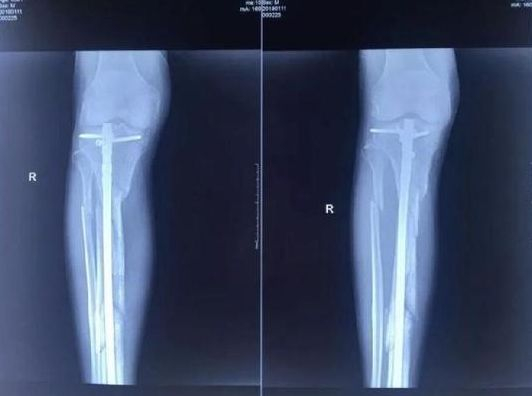

或许可从张毅的绝笔信里找到部分线索:信中提到,合伙人杨玉忠看到医院事业欣欣向荣,开始插手医院事务。由于不堪其扰,张毅自筹资金寻找场地重新组建城南医院。就在新医院即将开业的前夕,2017年10月18日,当张毅回到廊坊师范学院家里的楼下时,三个蒙面凶手(实际四人,有一人开车)一拥而上,把张毅按到在地进行殴打,并用事先准备好的铁镐把他的右腿打断成几节。

▲张毅生前遭人殴打致骨折。图片来自北京晨报